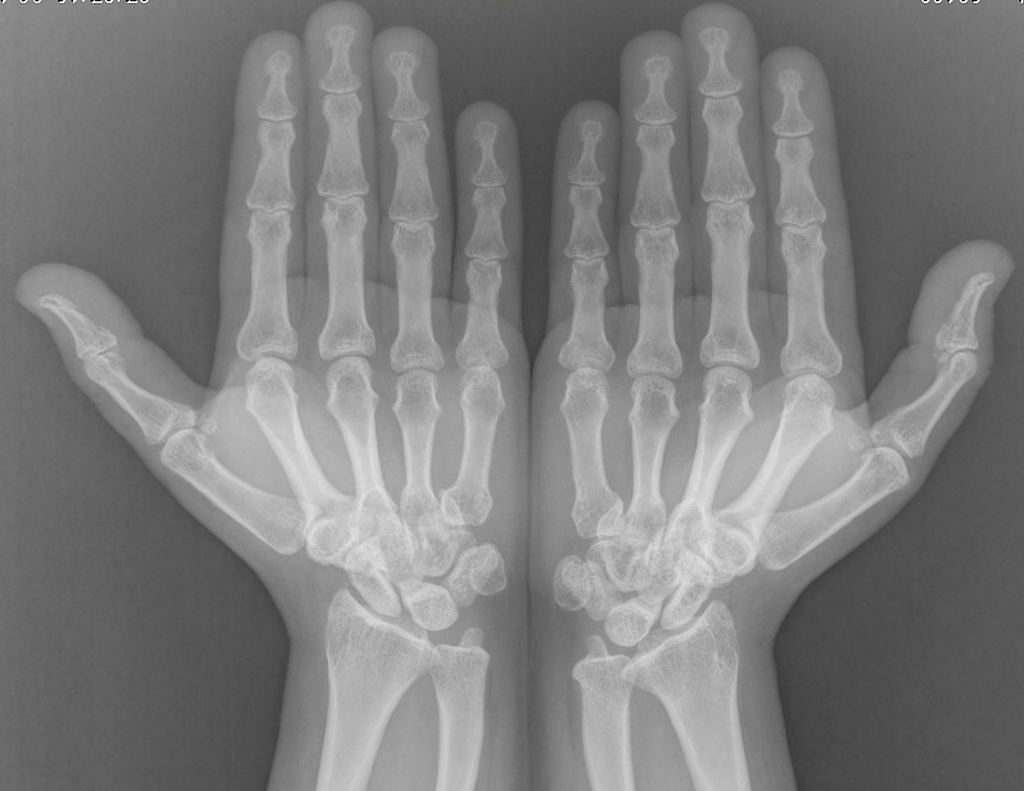

Short metacarpals in Turner syndrome Radiology Case Turner's Syndrome Radiology Classic sonographic findings of turner syndrome include diffuse fetal edema, cystic hygroma with septations, renal and cardiac anomalies such as horseshoe. Streak ovaries are a form of ovarian dysgenesis and are most commonly associated with turner syndrome, but can also be seen in. Turner syndrome is hypogonadism in phenotypica females due to partial or complete absence of one x chromosome,. Turner's Syndrome Radiology.

Short metacarpals in turner syndrome Artofit Turner's Syndrome Radiology Classic sonographic findings of turner syndrome include diffuse fetal edema, cystic hygroma with septations, renal and cardiac anomalies such as horseshoe. Rotator cuff denervation syndromes may be due to by a variety of causes, most important are: Turner syndrome is hypogonadism in phenotypica females due to partial or complete absence of one x chromosome, leading to short. Streak ovaries are. Turner's Syndrome Radiology.